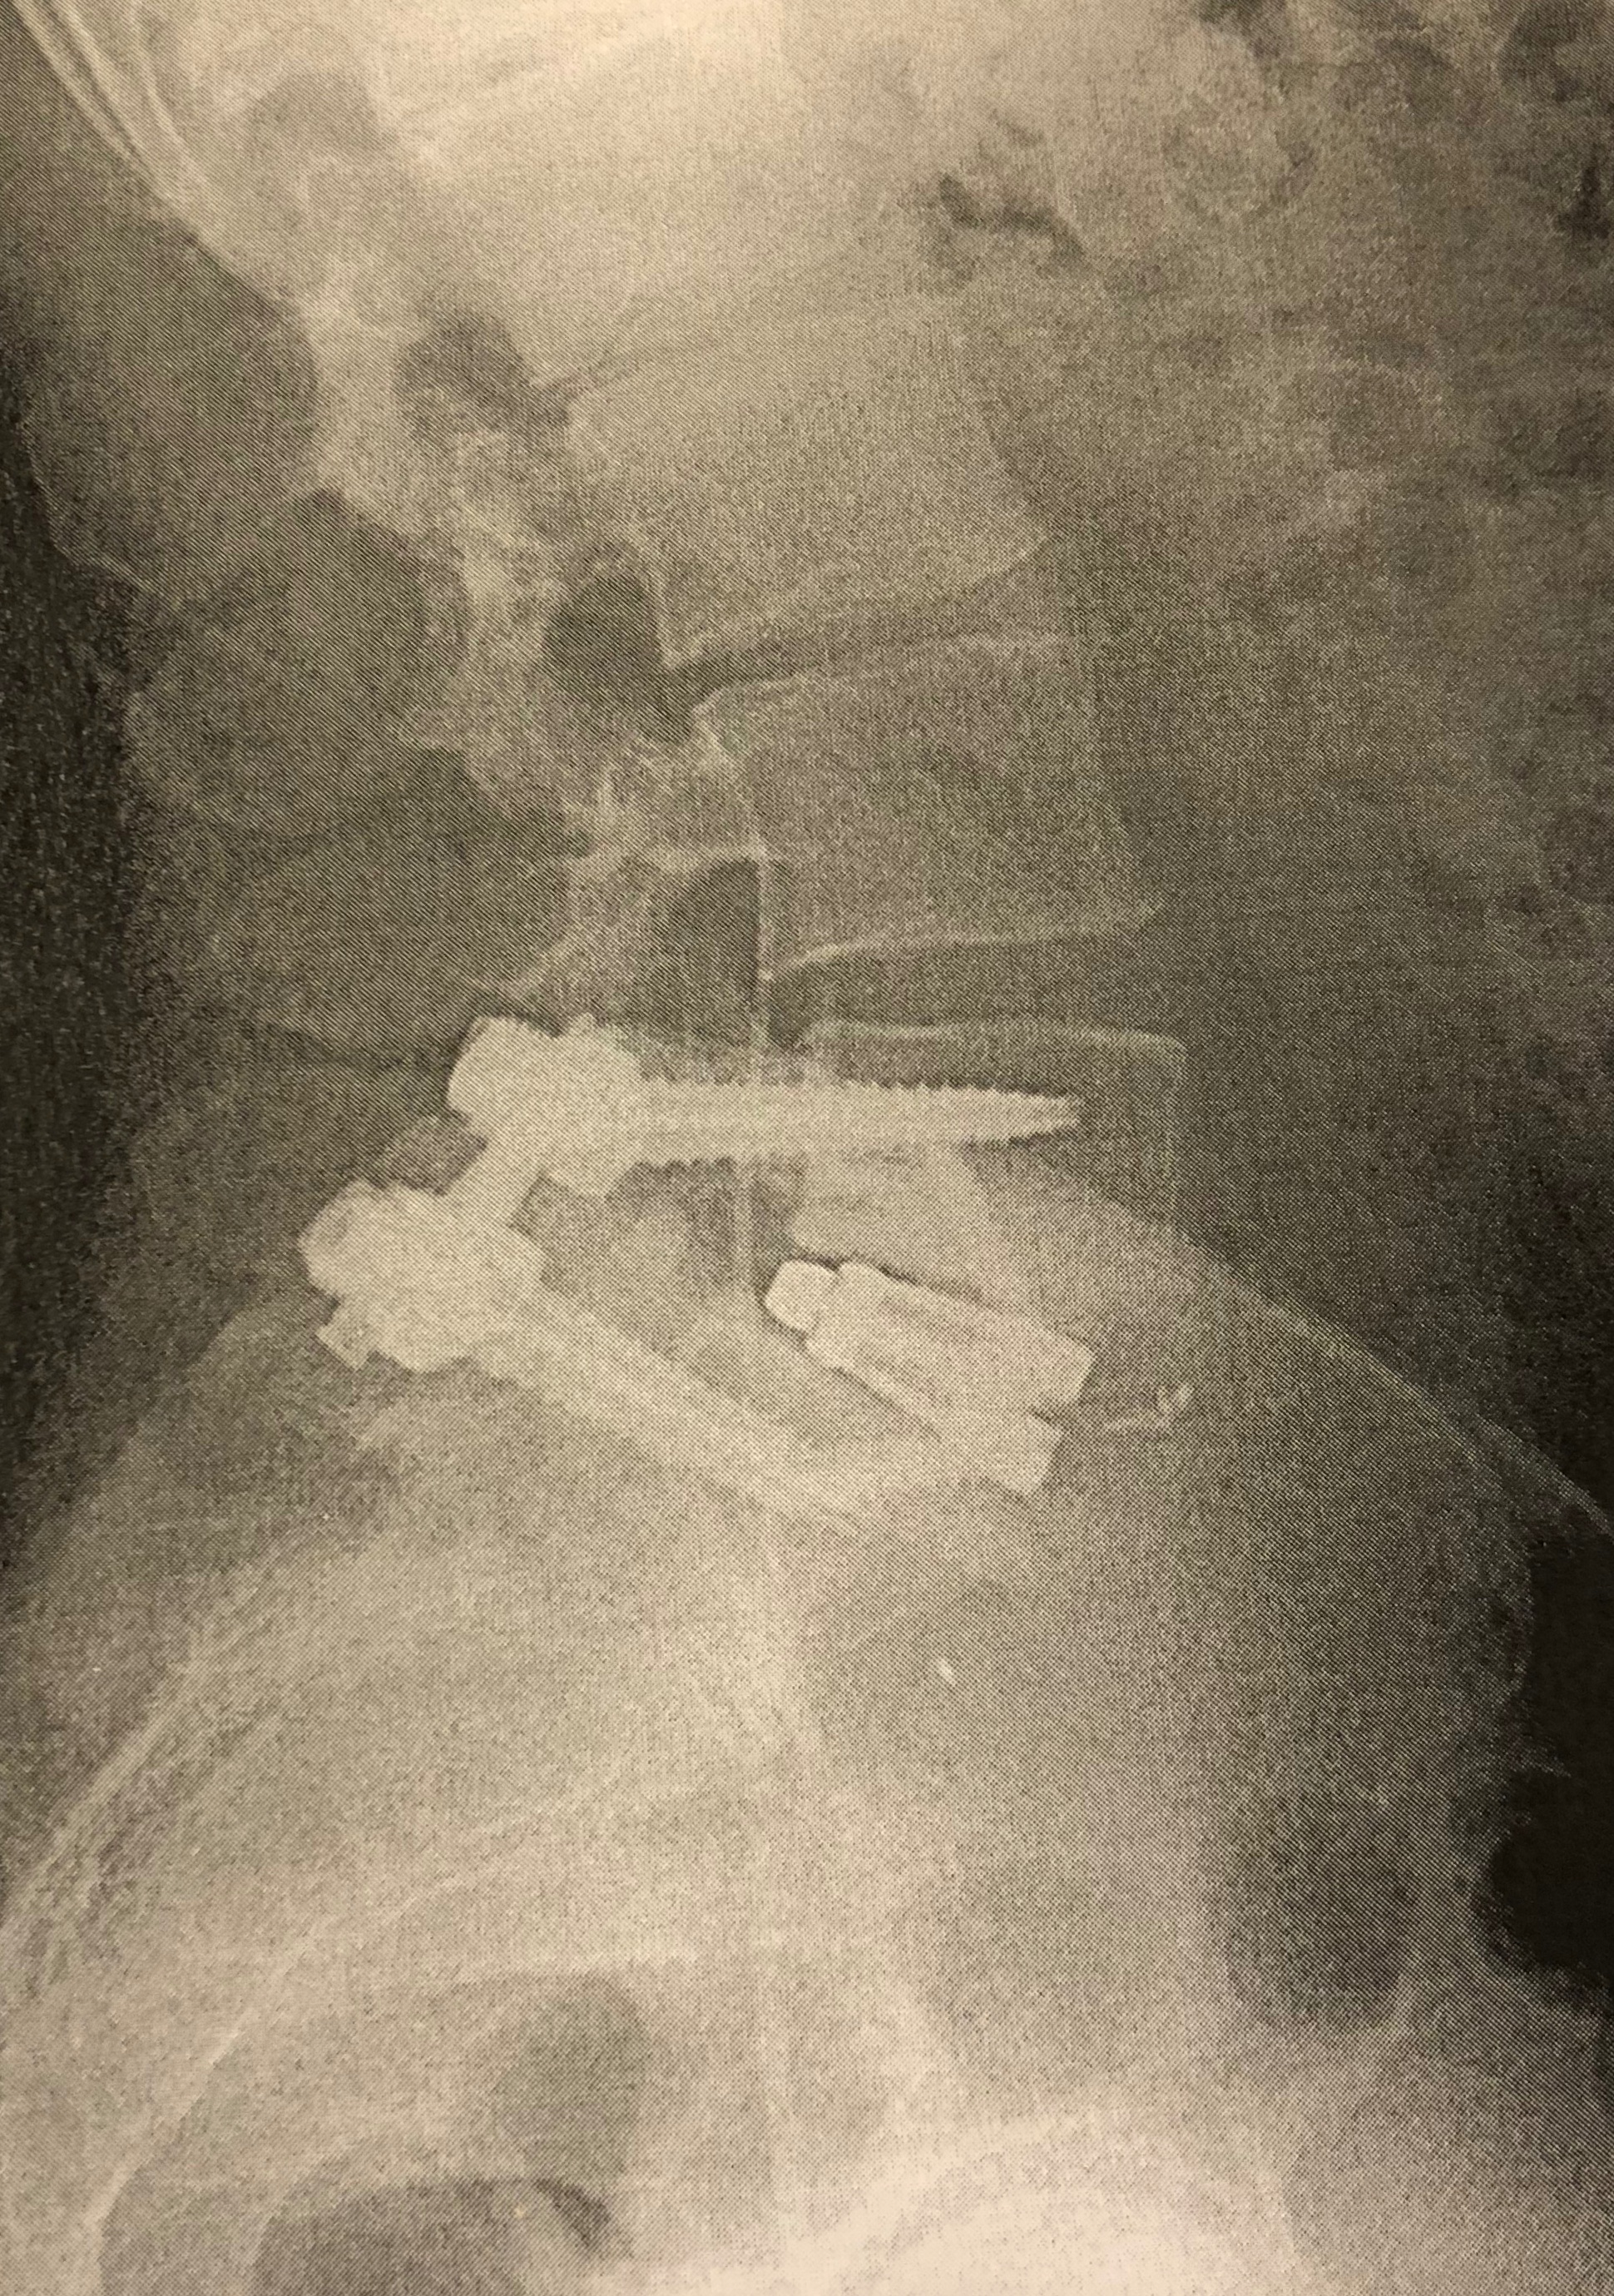

IMG_0306.jpeg